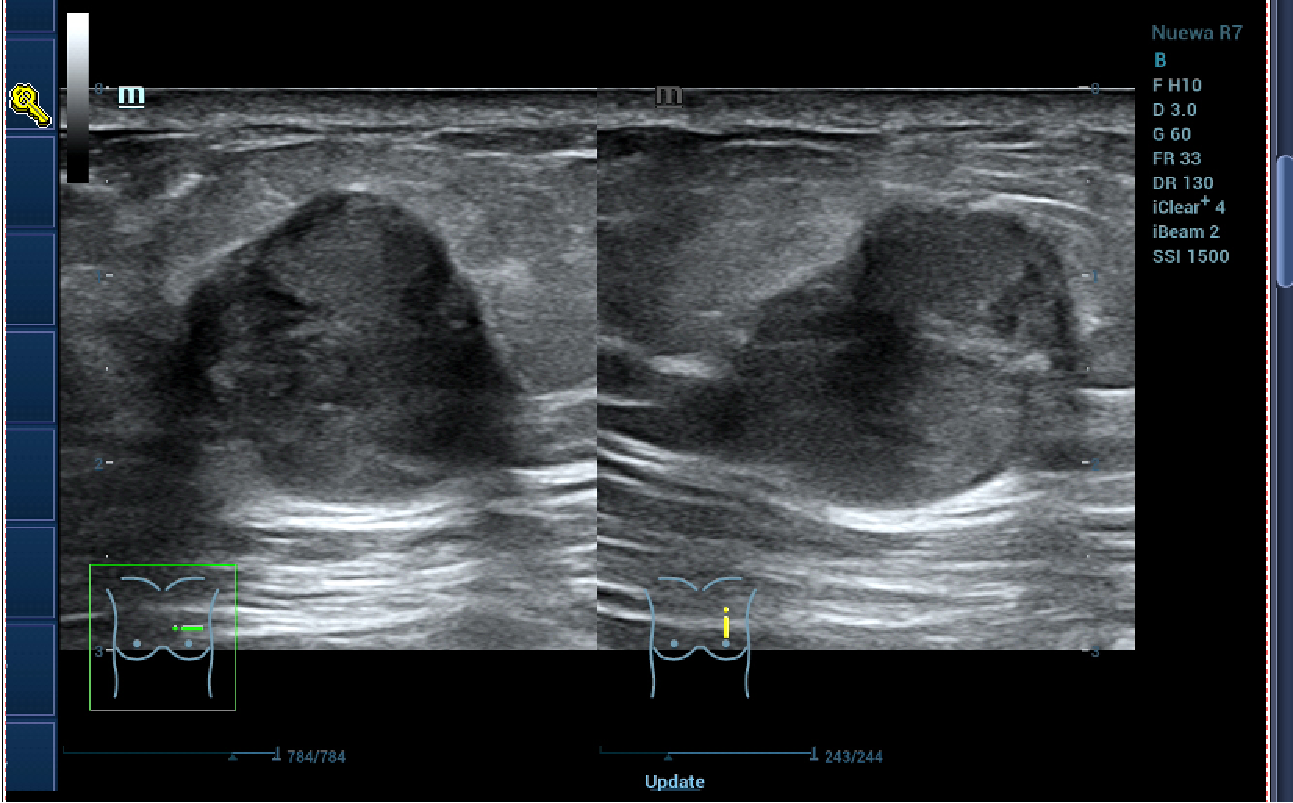

患者李女士(化名)在外院确诊为乳腺癌,这一消息让她及家人陷入巨大的焦虑与无助。经过多方咨询,李女士前来我院乳腺外科张永渠副主任门诊就诊。

乳腺彩超.png

乳腺彩超

经过对患者身体状况的全面评估,并了解到患者对切除乳房的担忧和恐惧后,张永渠副主任为李女士制订了“左乳癌保乳术+肿瘤整形+荧光辅助腋窝前哨淋巴结活检”个体化手术方案。为消除李女士及其家属的顾虑,张主任还通过可视化模型展示了手术原理及预后效果,分享相似病情患者的成功案例。张主任的专业与细致,让李女士重拾信心,最终决定接受手术